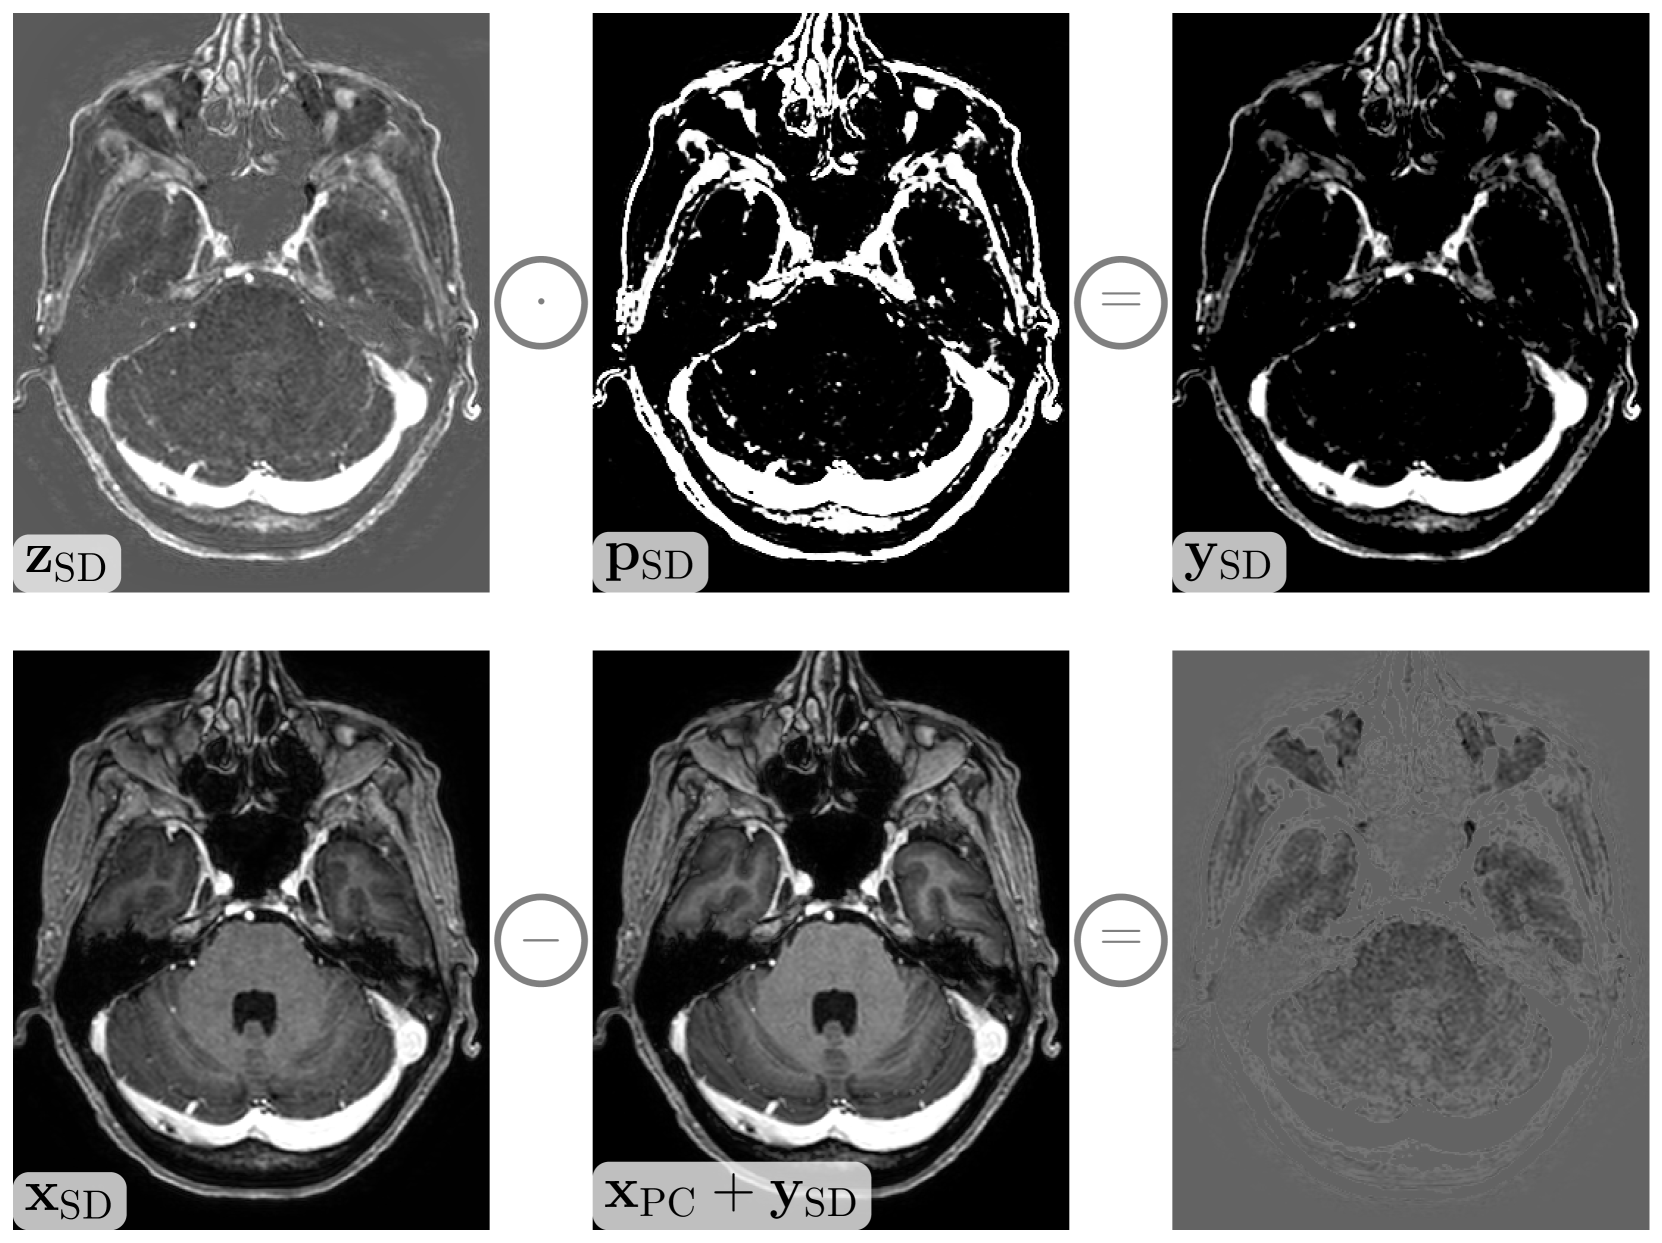

Figure 4 illustrates the contrast signal extraction steps for a prototypical case. As can be seen by the contrast signal image 𝐲SDsubscript𝐲SD\mathbf{y}_{\mathrm{SD}}bold_y start_POSTSUBSCRIPT roman_SD end_POSTSUBSCRIPT on the right of the first row, the noise is almost completely suppressed, while the CE signal is preserved. The second row compares the standard-dose image 𝐱SDsubscript𝐱SD\mathbf{x}_{\mathrm{SD}}bold_x start_POSTSUBSCRIPT roman_SD end_POSTSUBSCRIPT, utilized as ground truth in previous approaches, and our implicit standard-dose image generated by adding the CE signal to the pre-contrast image, i.e. 𝐱PC+𝐲SDsubscript𝐱PCsubscript𝐲SD\mathbf{x}_{\mathrm{PC}}+\mathbf{y}_{\mathrm{SD}}bold_x start_POSTSUBSCRIPT roman_PC end_POSTSUBSCRIPT + bold_y start_POSTSUBSCRIPT roman_SD end_POSTSUBSCRIPT. These images essentially differ only in the non-enhancing regions due to noise and inhomogeneities of the bias field. By using the contrast signal 𝐲SDsubscript𝐲SD\mathbf{y}_{\mathrm{SD}}bold_y start_POSTSUBSCRIPT roman_SD end_POSTSUBSCRIPT as ground truth, we avoid learning to predict the degradations shown in the bottom-right image.

Refer to caption

Figure 4: The top row depicts the contrast signal extraction from the standard-dose subtraction image 𝐳SDsubscript𝐳SD\mathbf{z}_{\mathrm{SD}}bold_z start_POSTSUBSCRIPT roman_SD end_POSTSUBSCRIPT. The pixel-wise multiplication with the CE mask 𝐩SDsubscript𝐩SD\mathbf{p}_{\mathrm{SD}}bold_p start_POSTSUBSCRIPT roman_SD end_POSTSUBSCRIPT yields the target contrast signal image 𝐲SDsubscript𝐲SD\mathbf{y}_{\mathrm{SD}}bold_y start_POSTSUBSCRIPT roman_SD end_POSTSUBSCRIPT. The bottom row visualizes the differences between the standard-dose image 𝐱SDsubscript𝐱SD\mathbf{x}_{\mathrm{SD}}bold_x start_POSTSUBSCRIPT roman_SD end_POSTSUBSCRIPT and the standard-dose image implicitly generated by adding the contrast signal to the pre-contrast image 𝐱PC+𝐲SDsubscript𝐱PCsubscript𝐲SD\mathbf{x}_{\mathrm{PC}}+\mathbf{y}_{\mathrm{SD}}bold_x start_POSTSUBSCRIPT roman_PC end_POSTSUBSCRIPT + bold_y start_POSTSUBSCRIPT roman_SD end_POSTSUBSCRIPT. Note that both standard-dose images only differ by the noise in non-enhancing regions.